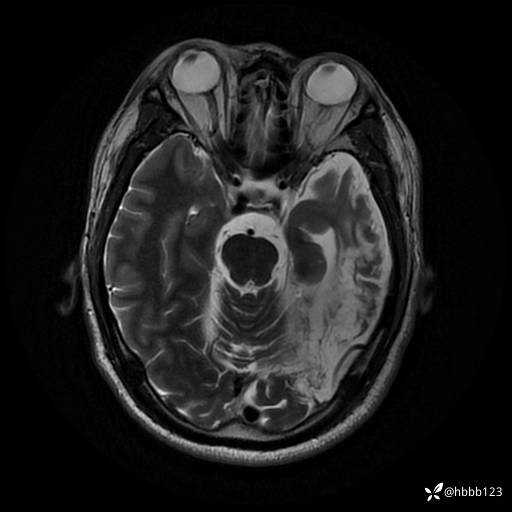

T2: